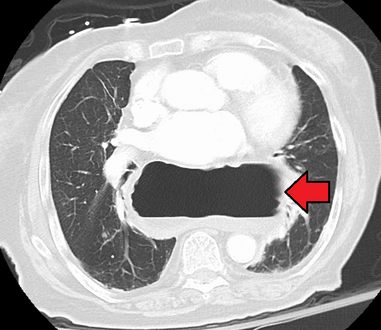

وفي الوقت نفسه، يمكن لقياس الضغط تحديد سلامة حركات المريء ووجود ارتخاء المريء. وتسمح اختبارات الأس الهيدروجيني بالتحليل الكمي لنوبات الارتجاع الحمضي. كما أن التصوير المقطعي المحوسب مفيد في تشخيص مضاعفات الفتق الحجابي مثل الالتواء المعدي، واسترواح الصفاق، واسترواح المنصف.[8]

فتق حجابي كبير في صورة للصدر بالأشعة السينية، حيث يُميز بأسهم مفتوحة على النقيض من حدود القلب التي تتميز بأسهم مغلقة.